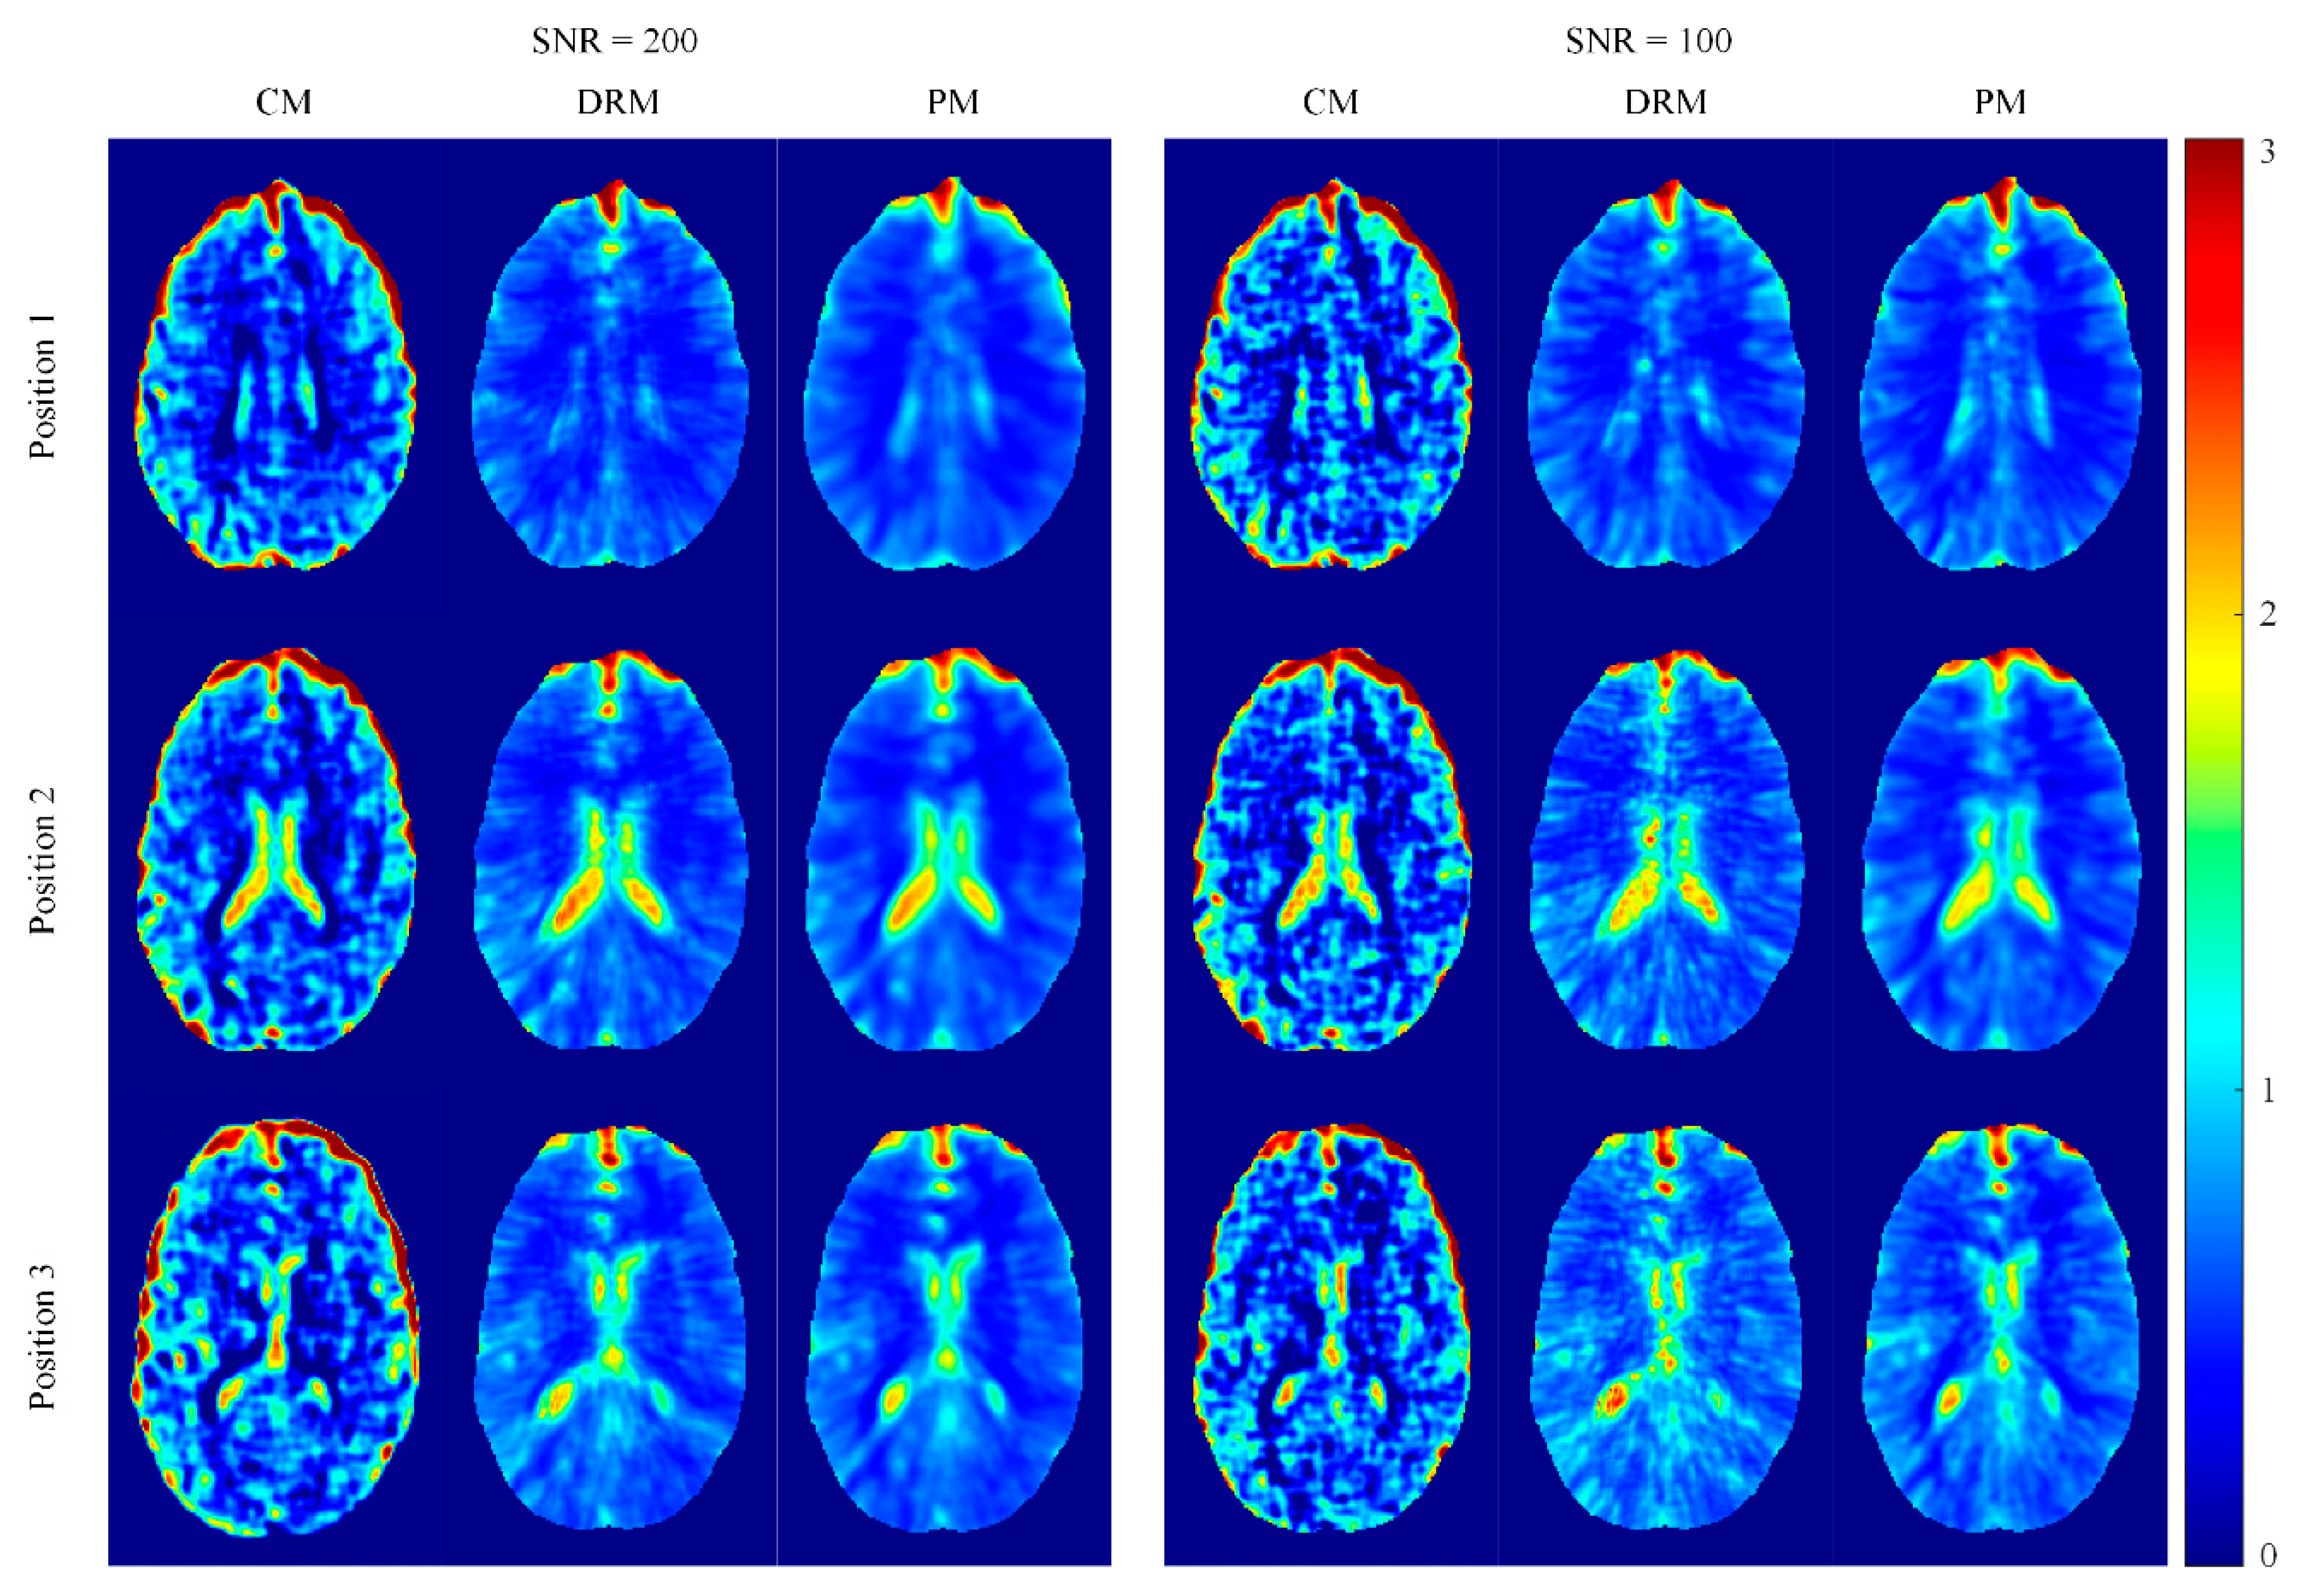

4.2. Ella Head Simulation Results